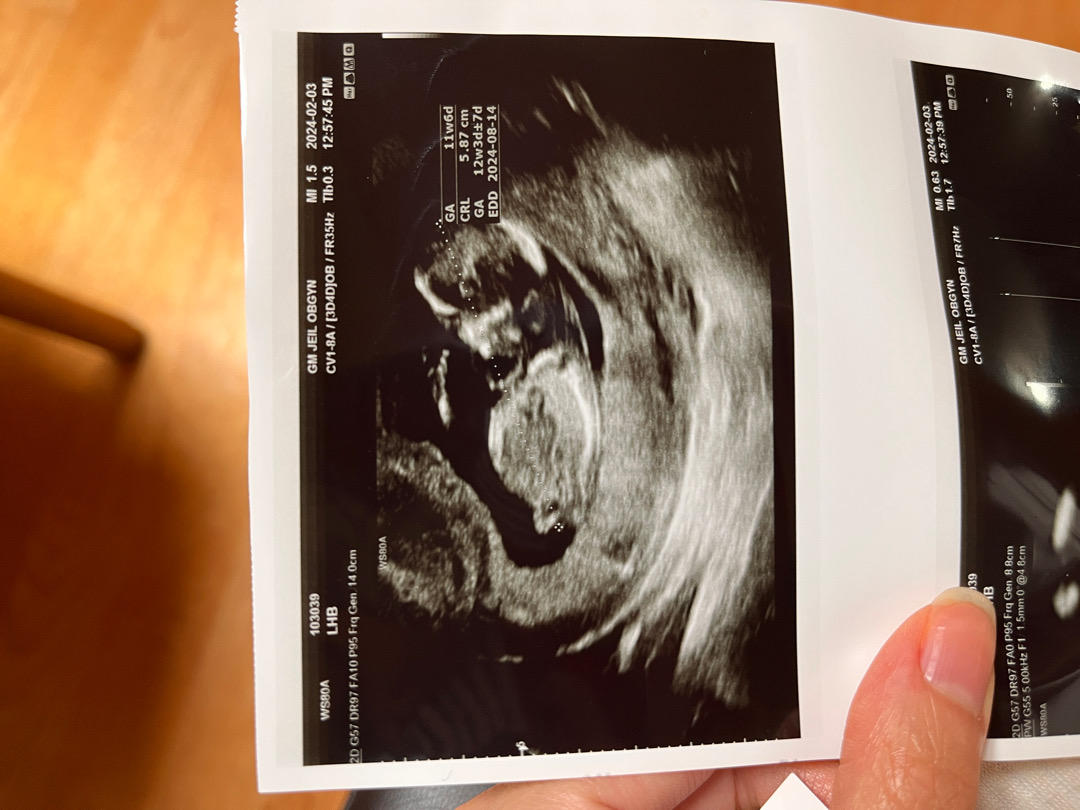

성별 너무 궁금하네용 ㅠㅠ

각도법이 애매해서 ㅎㅎ 지금 13주인데 12주차에 찍은 사진이에요! 각도법 봐주세용!!!